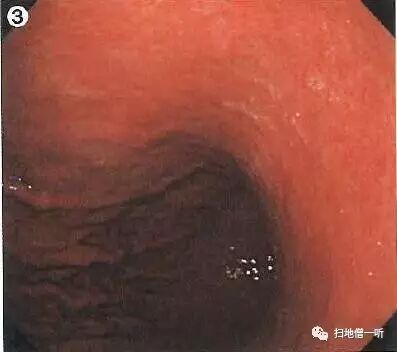

A:胃癌在图3及图6。HP未感染胃癌。

胃粘膜RAC阳性表现,提示HP未感染粘膜。胃体下部小弯侧可见小片状褪色粘膜。图3和图6是两个角度观察同一处病变。

靛胭脂喷洒然后后边界不清,表面无凸凹变化,为IIb型病变。无萎缩的胃底腺区域发现退色调病变,应怀疑印戒细胞癌。

最终病理诊断:

胃体下部小弯,O-IIb,4mm,sig,T1a (M),UL(-)

小结:HP未感染背景下退色调病变应注意着重观察。

其他图片补充说明:

图1可见胃窦部条带形发红,靛胭脂染色后更加清晰,被定义为术语:条带状发红,此为HP阴性所见粘膜像。

胃体上部大弯侧可见山田II型胃底腺息肉,边界清晰,表面光滑,此亦提示HP阴性粘膜征象。